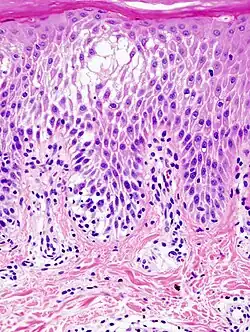

La espongiosis se observa cuando se estudian muestras de una biopsia de piel a través del microscopio, En la capa de Malpigio, las células están más separadas de lo normal y pueden formarse pequeñas vesículas por acumulación de líquido, observándose además la presencia de células inflamatorias como linfocitos.